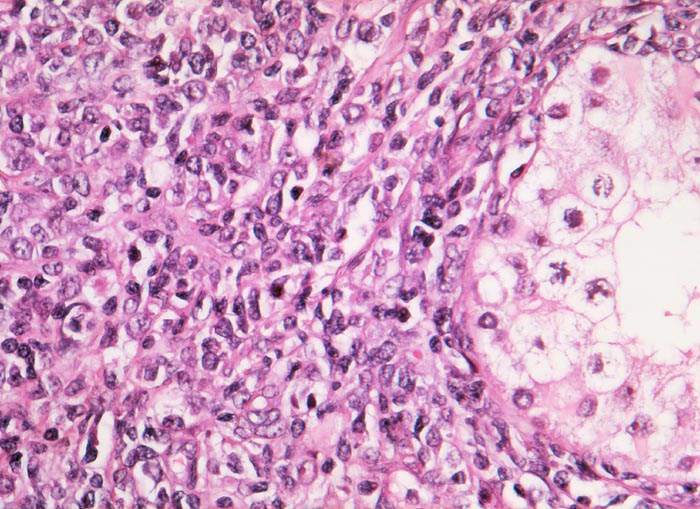

Diffuses grosszelliges B-Zell Lymphom

Hoden

Rechts im Bild der Anschnitt eines erhaltenen Hodentubulus. Im Interstitium ein diffuses Infiltrat von mittelgrossen bis grossen Lymphomzellen mit grossen blasigen Kernen und teilweise prominenten Nukleolen.

Die Abgrenzung eines Seminoms oder embryonalen Karzinoms von einem hämatologischen Tumor kann schwierig sein, wenn man nicht daran denkt. Bei älteren Männern sind Keimzelltumoren abgesehen vom spermatozytischen Seminom sehr selten.